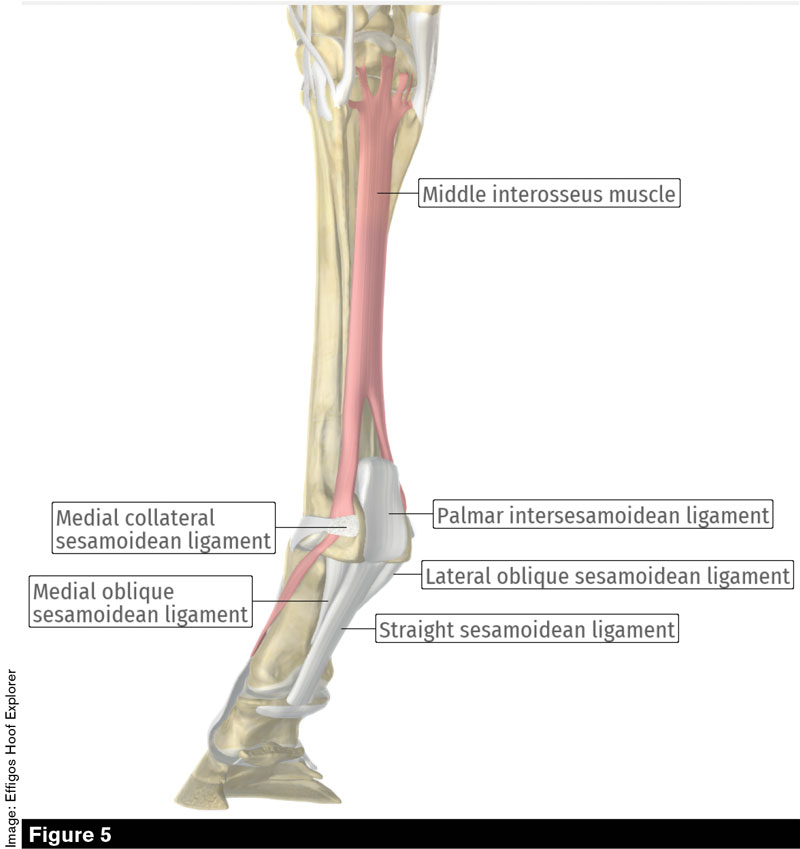

ar.inspiredpencil.comMichael Porter, Equine Veterinarian: Plantar Annular Ligament Desmitis

ar.inspiredpencil.comMichael Porter, Equine Veterinarian: Plantar Annular Ligament Desmitis

michaelporterdvm.blogspot.complantar horse ligament annular equine